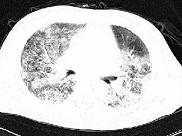

问题 男性,42岁,近2年来无明显诱因反复出现咳嗽,痰少,活动后气促,无发热,无胸痛,无咯血,心电图及心脏彩超未见异常,肺功能FEV1.901,FVC2.001,DLco下降,支气管激发试验阴性。胸部CT见图,该患者最有可能是下列哪一种疾病 ( )

选项 A.支气管哮喘 B.慢性阻塞性肺疾病 C.支气管扩张 D.支气管肺癌 E.特发性间质性肺炎

答案 E